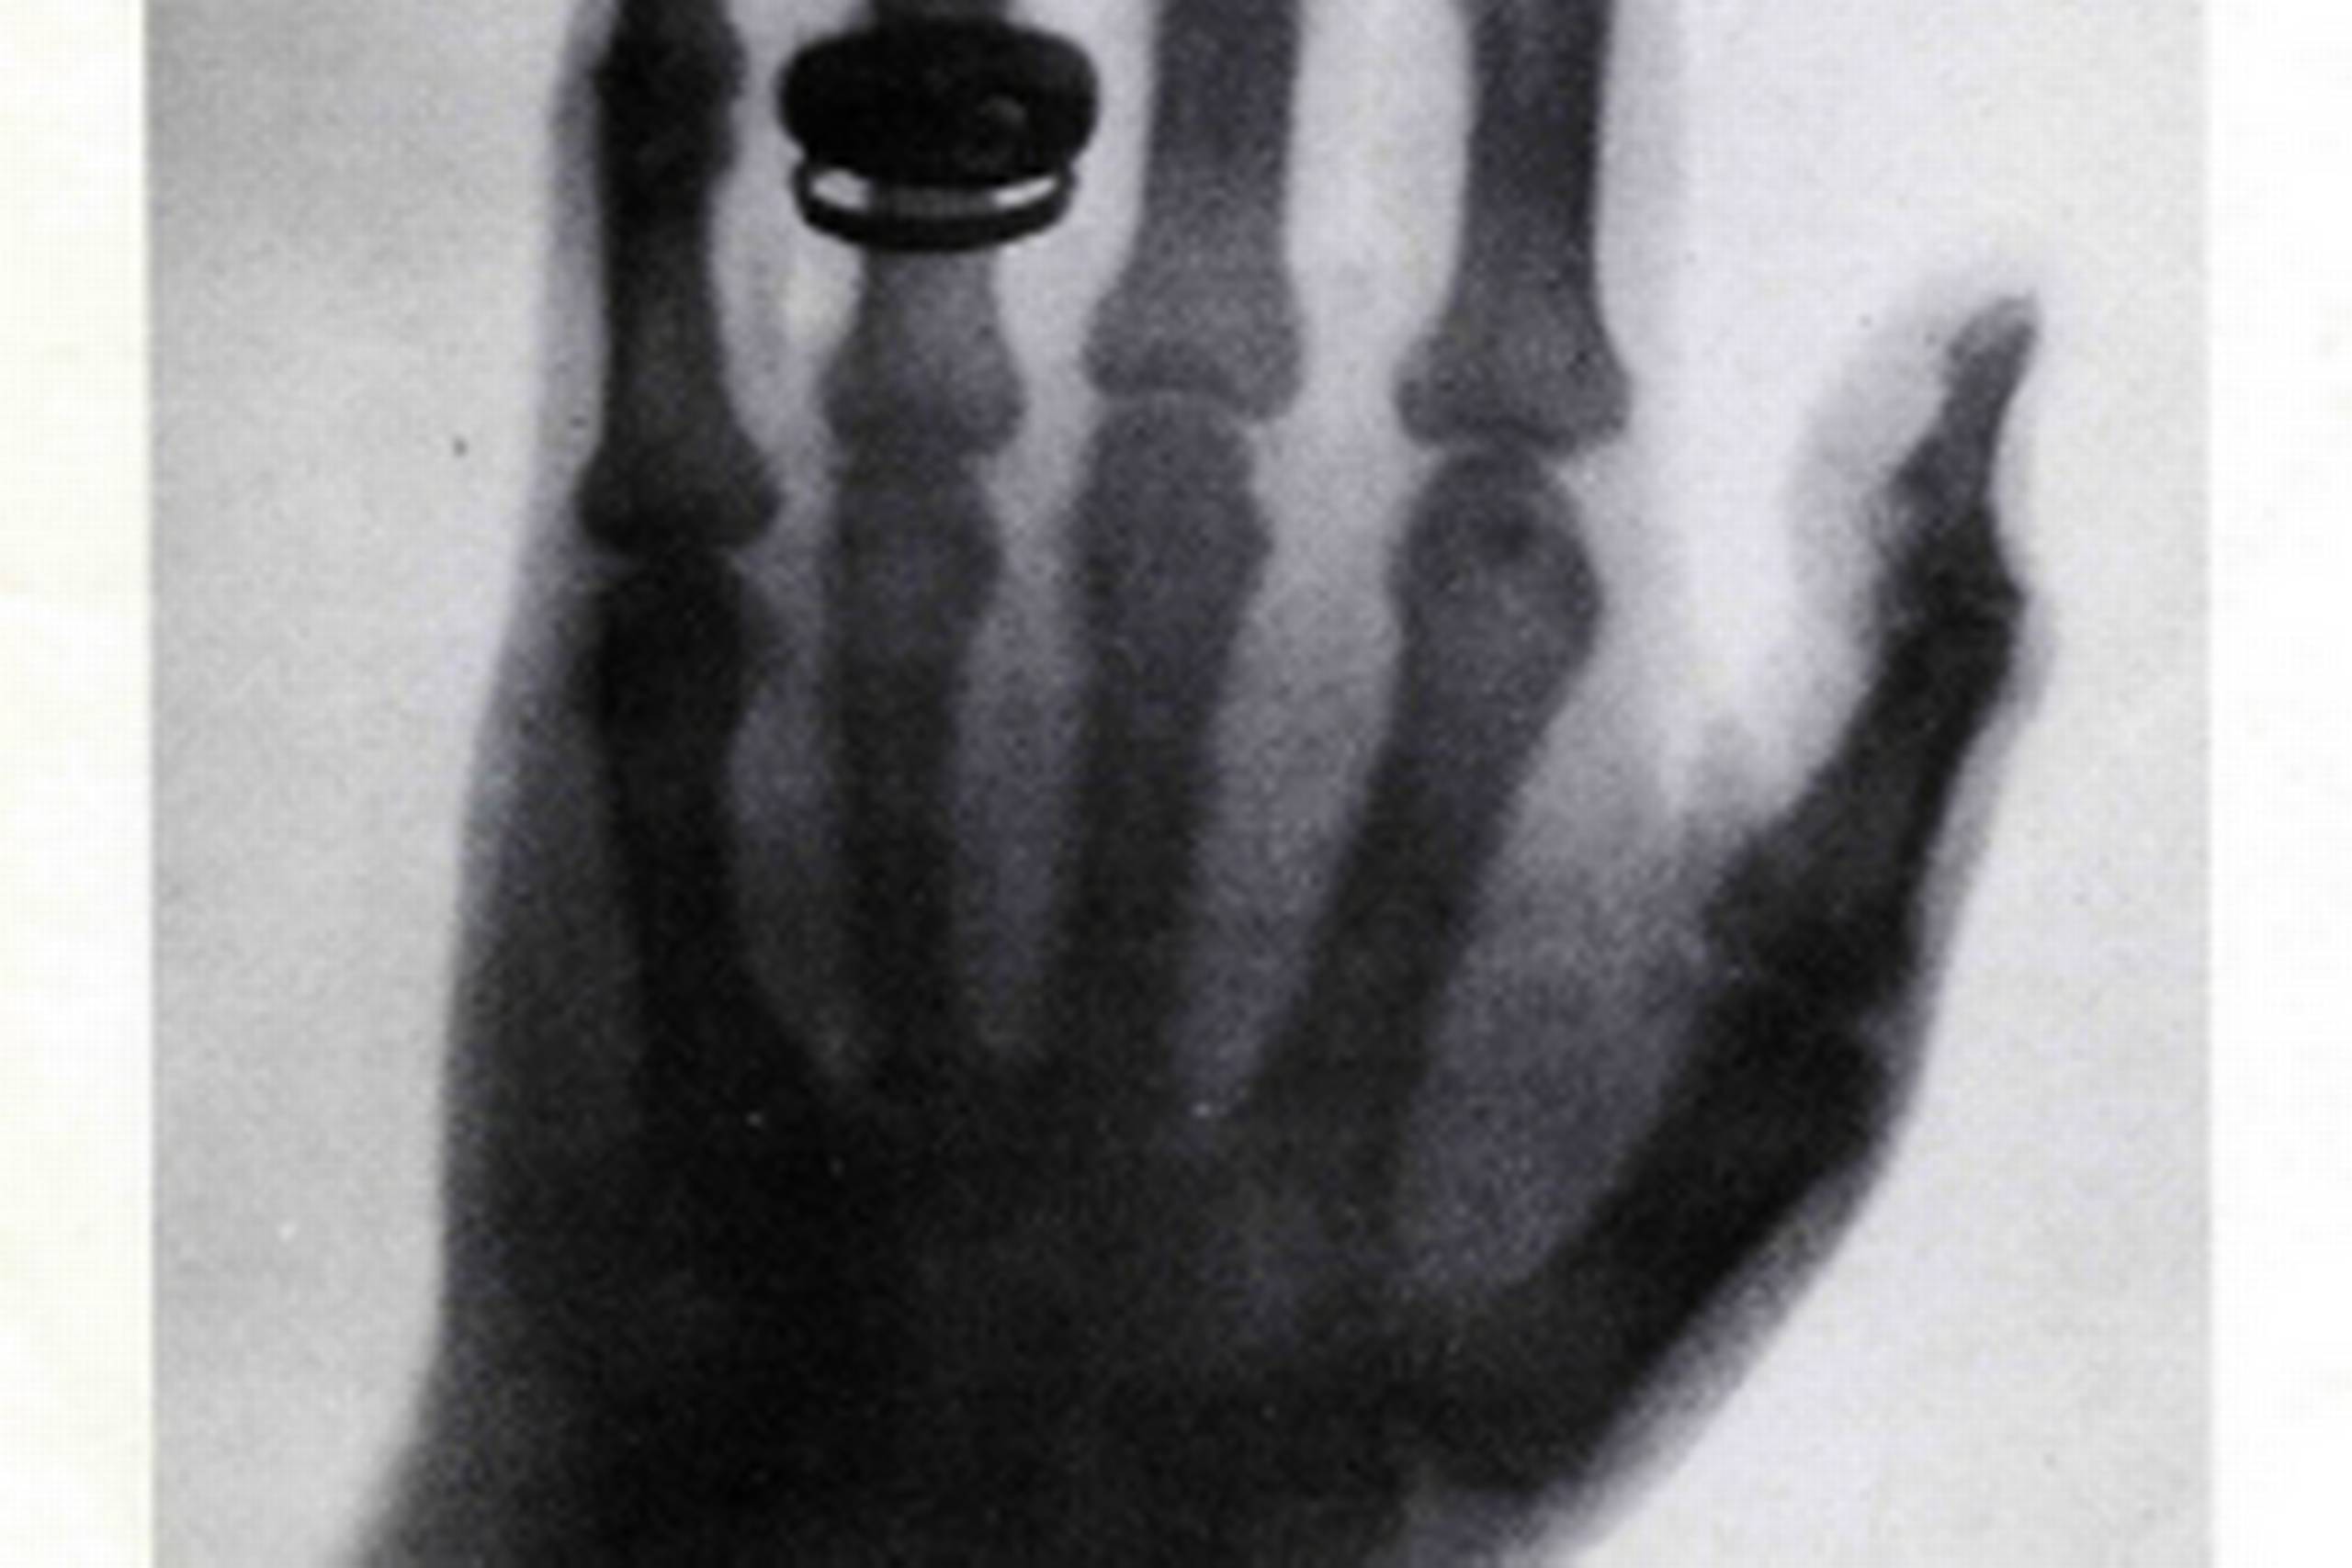

25. Professor Röntgens usynlige stråler